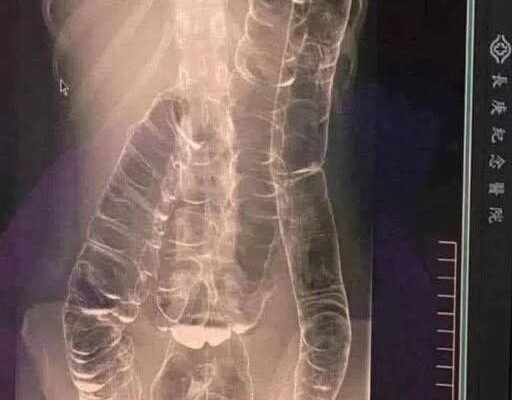

When waste accumulates in the colon due to an inefficient digestive system, it causes severe discomfort and bloating. Over time, the colon expands beyond its normal size, struggling to contain the excessive buildup of feces. In this case, medical imaging revealed a severely distended colon that had enlarged so much it reached up toward the chest, dangerously close to the heart. The stretching had nearly erased the colon’s natural folds and wrinkles, essential for its proper function. Left untreated, this condition could have led to life-threatening complications.